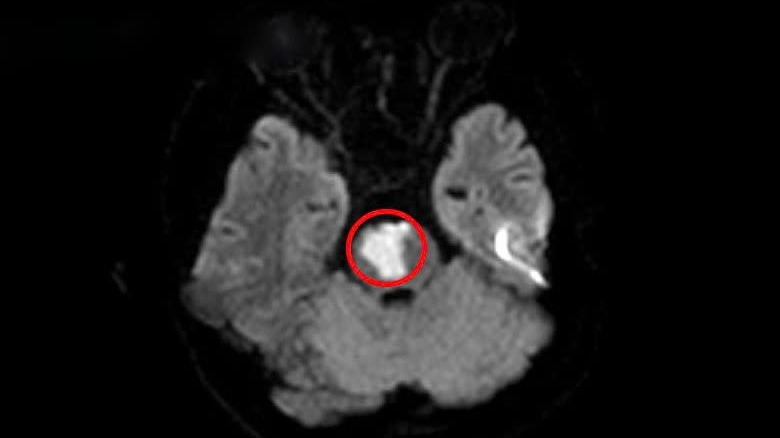

Sau khi khám nghiệm tử thi, kết quả cho thấy nguyên nhân tử vong của Tiểu Trương là do lệch khớp cổ, viêm cột sống cổ gây nhồi máu não và gây rối loạn chức năng hệ thần kinh trung ương. Bên cạnh đó, Tiểu Trương cũng có những dấu hiệu của căn bệnh thoái hóa đốt sống cổ, do làm việc máy tính quá nhiều.